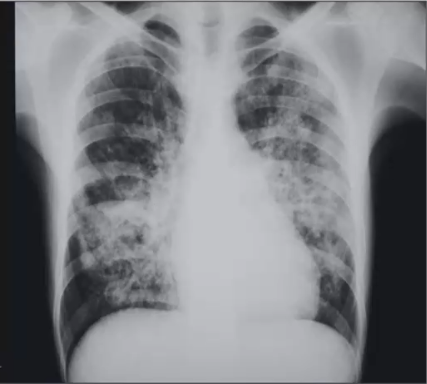

❖ 胸部X线检查(简便、廉价,对细

❖ 小病灶和病灶细微表现显示欠缺,初步筛查)

❖ CT平扫(结节、肿块样、实变、磨玻璃影、晕征、反晕征等)